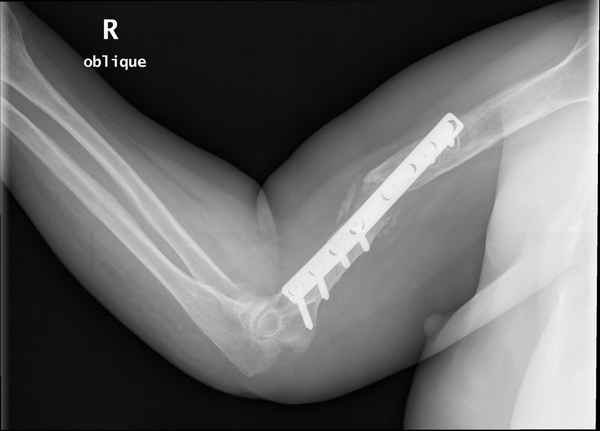

Больная 48 лет, медсестра-массажист, перелом плеча 7 лет назад, оперирована 4-кратно и безуспешно

Больная 48 лет, медсестра. Травма получена 7 лет назад, оперирована первично в Турции - остеосинтез пластиной - несращение - реостеосинтез стержнем там же через год (обычным, с выстоянеием его в полость плеча) - несращение - поступила к нам впервые в марте 2008 года - удаление стержня, реостеосинтез пластиной и костная пластика, в течение 2 лет лизис кости вокруг винтов, смещение фиксатора, в марте 2010 - удаление пластины, реостеосинтез интрамедуллярным стержнем с блокированием (рассверливание + костная пластика). В динамике - вновь лизис в области перелома, нестабильность дистальных блокирующих винтов.

Уважаемый коллега. Ось и длина конечности сохранены. Фиксация, согласно снимков, стабильная. Проводить дополнительные операции считаю нецелесооразным. Можно применить бифосфонаты, желательно 1-2 поколения (бонефос), в\в в условиях интенсивной терапии, они довольно агрессивно и быстро кальцинируют именно остеопоротичную кость, желательно проконсультироватся с коллегами онкологами у которых есть опыт применения. Бифосфонаты 3-4 поколения можно давать годами с увеличением костной массы на 3-5% в год.

Клинически фиксация пока действительно стабильна, но на рентгенограммах резорбция кости в области дистальных блокирующих винтов и миграция одного из них.